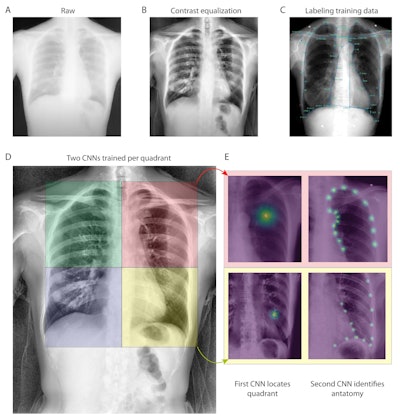

(a) Raw example of a dynamic digital radiograph. (b) Contrast equalization using contrast-limited adaptive equalization shows improved anatomical visualization. (c) Training data is generated through manually labeling using SLEAP’s graphical user interface. (d-e) Neural network detection schematic. For each quadrant a series of two networks were used. The first identifies the quadrant center, the second using input of the first, then identifies individual anatomical landmarks within a quadrant. (d) Four neural networks were trained, each with the objective of identifying a chest quadrant centroid. The four separate quadrants are visualized as colored boxes (right upper quadrant, green; right lower quadrant, blue; left upper quadrant, red; left lower quadrant, yellow). (e) Serial centroid then anatomical identification. Two quadrant examples showing confidence maps of trained neural networks identifying quadrant centroids (left) and then anatomical confidence maps (right). Image and caption courtesy of Chest Pulmonary.